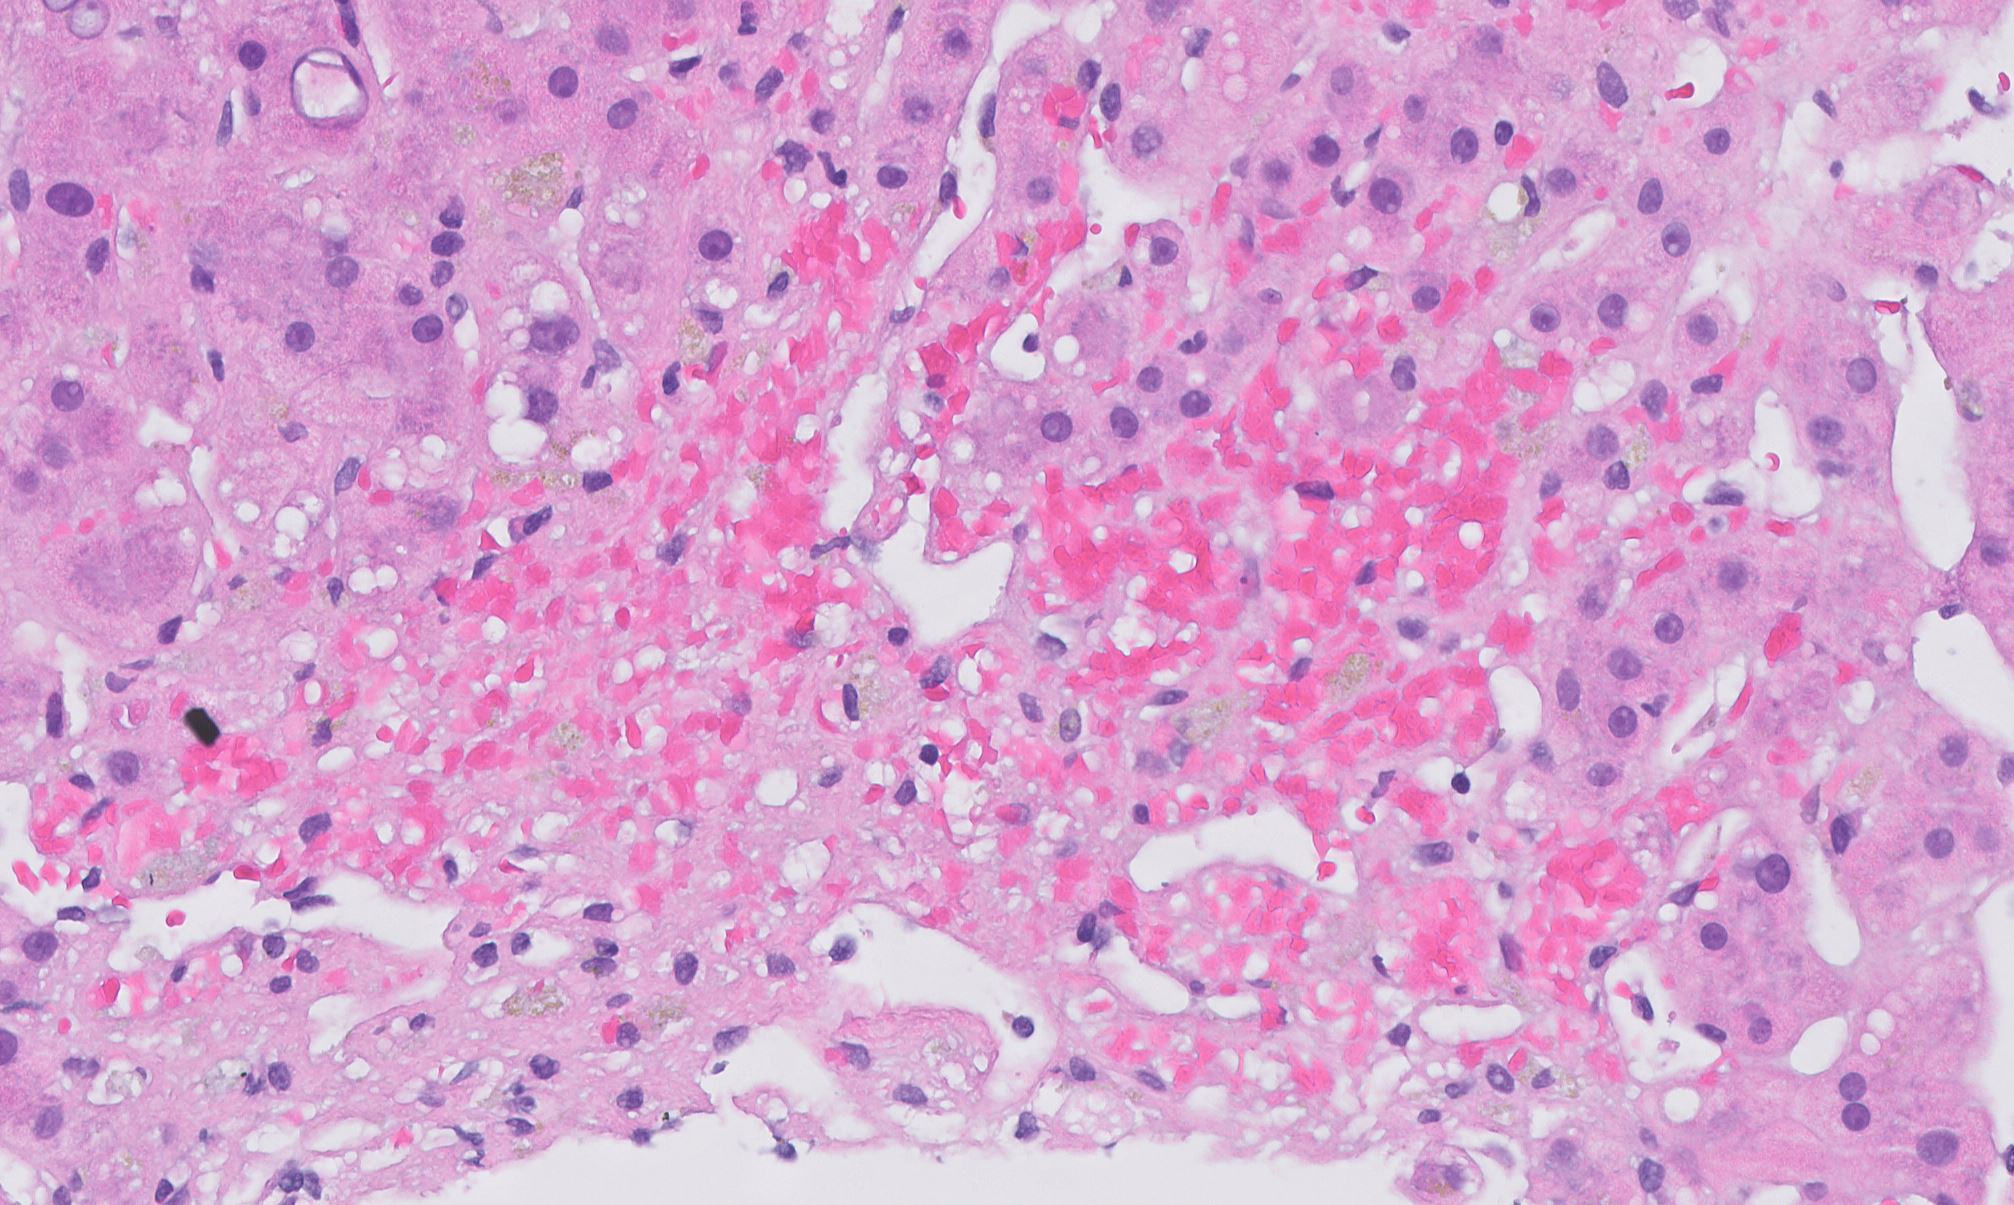

Chronic Venous Congestion (Liver)

- 1Dilated central veins and sinusoids

- 2Centrilobular haemorrhagic necrosis (zone 3)

- 3Periportal fatty change (zone 1)

Chronic venous congestion of the liver (cardiac liver) results from right-sided heart failure causing chronic back-pressure in the hepatic veins. Grossly it produces the 'nutmeg' pattern; histologically there is dilated central veins and sinusoids, centrilobular haemorrhagic necrosis, periportal fatty change, and preserved portal triads.

- Centrilobular haemorrhagic necrosis (zone 3 hepatocytes)

- Eosinophilic hepatocyte cytoplasm in zone 3

- Fatty changes in periportal (zone 1) hepatocytes

Right heart failure → elevated right atrial pressure → retrograde transmission to hepatic veins → sinusoidal congestion → ischaemic necrosis of centrilobular hepatocytes (zone 3, farthest from portal blood supply). Atrophied hepatocytes with haemorrhagic necrosis appear red; preserved periportal hepatocytes with fatty change appear yellow — producing the nutmeg pattern.